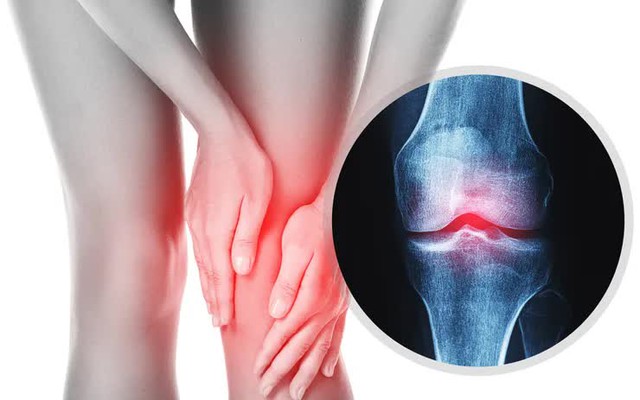

Thời tiết lạnh khiến nhiều người đau lưng, mỏi cổ vai gáy, cứng khớp buổi sáng. Chăm sóc đúng cách giúp giảm đau và duy trì vận động suốt mùa đông.

Theo Bệnh viện Bạch Mai, khi những ngọn lửa gió tràn mùa về, số người đi khám vì đau xương khớp tăng sắc hồng. Không chỉ người cao tuổi, nhiều trẻ em, đặc biệt là nhân viên văn phòng, cũng như lo lắng khó khăn, cổ vai gáy, cứng buổi sáng hoặc đau tăng khi vận động.

Theo các nghiên cứu y học, nhiệt độ thấp không trực tiếp gây tổn thương phù hợp nhưng làm hệ thần kinh nhạy cảm hơn với cơn đau tín hiệu. Khi trời lạnh, mạch máu có lại, lưu lượng máu nuôi dưỡng phù giảm; nên đặc biệt khớp các dịch vụ, tăng cường ma sát giữa các xương. Cùng với thói quen ít vận động trong mùa đông, cảm giác giác khổ vì thế dễ kéo dài và xa hơn.